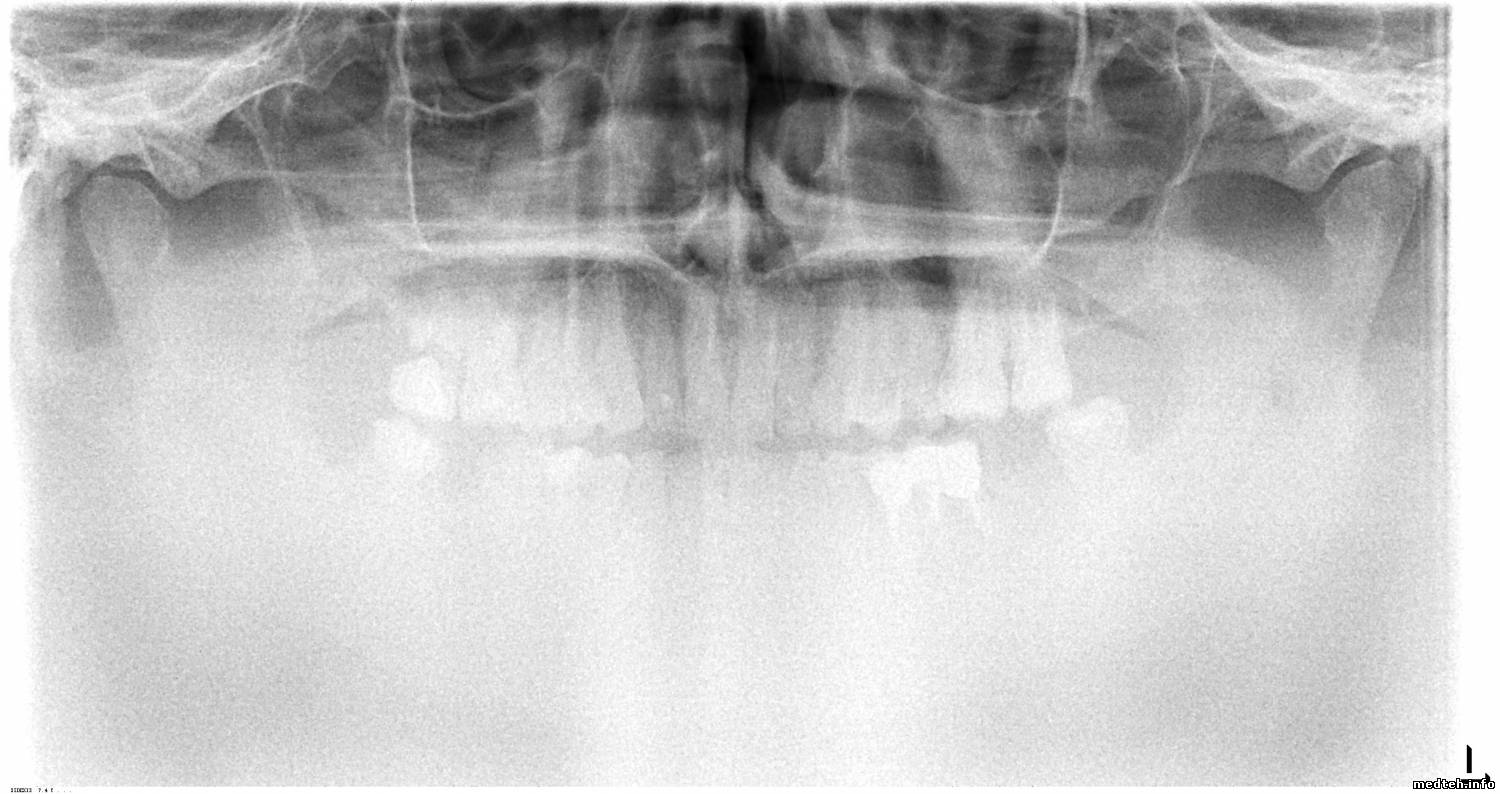

Ортопантомографу Orthophos XG 3 немецкой компании Sirona Dental Systems GmbH около 3-х лет, сделано 2700 снимков.

Вчера вдруг стал выдавать снимки с низким контрастом, в нижней части снимка вообще ничего не разобрать.

Ошибок никаких не выдаёт.

Что могло произойти?

Orthophos XG 3D от Sirona. Плохое качество изображения.

Подскажите, пожалуйста, в чём может быть проблема?

Фото прилагаю:

1605363.jpg (270.0 Kb) · 6676121.jpg (173.7 Kb) · 8381895.jpg (212.7 Kb)

Фото прилагаю.

Goodboy03, по 3D снимку: проверить ошибки в логе аппарата, потом, скорее всего, калибровка. Потом по результату.

По панораме:

1. Матрицы датчика либо всё, либо датчик крепко тряхнули/ударили, что на OPXG3D сделать сложновато.

Есть вероятность, что окислы на разъёмах частей матрицы, для этого надо разбирать датчик, однако немцы это не рекомендуют;

2. Есть очень маленький шанс, что проблема в кабеле поворотного модуля датчиков.